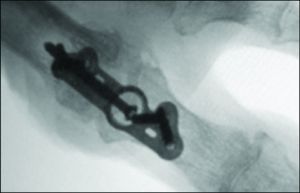

A recently introduced plating system can give surgeons a clearer view of post-op healing.

CoLink® View Bone Plates combine titanium metal and polyether ether ketone (PEEK), a high-performance polymer, which is transparent to X-rays, unlike traditional metal plates, according to the manufacturer In2Bones. The company says the plates provide transverse joint compression and surgeons can see the bone fusion site as it heals postoperatively.

In2Bones says the PEEK in CoLink View is also less stiff than metal implants and is closer to the elasticity of bone. The company adds that implants made of metal would not have positive elasticity and thus would lead to slower healing.